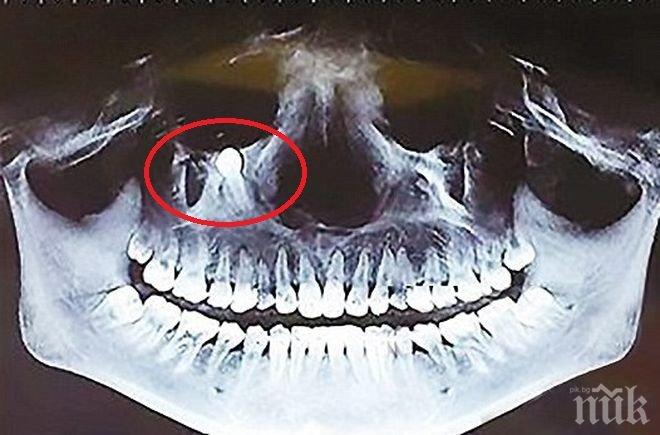

Рядък случай в медицинската практика бе регистриран в болницата на китайския град Чунцин, съобщиха местни медии. Хирурзи са отстранили трисантиметров зъб от устата на китайско момиче, защото той тръгнал да расте към окото й.

Пациентката се оплаквала от месеци, че трудно дъвче и дори се е отказала от твърда храна поради това. След обстоен преглед се установило, че това се дължи на зъб, който расне не в нормалната посока, а към окото й.

Вероятността той да повреди зрението на момичето била голяма и затова операцията по отстраняването му станала неизбежна. Тя преминала успешно и момичето вече се чувства добре. Заключението на лекарите за уникалиня случай е, че млечните зъби не са паднали навреме и така са попречили на израстването на постоянните. Затова един от тях просто е променил посоката на растеж.